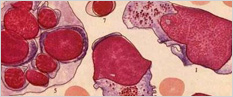

中西三联净血免疫疗法"治疗过敏性紫癜,从患者体内提取T细胞,通过特色免疫方法 阻断病变细胞的分化、增殖、侵袭,然后结合中西医治疗血液病精髓,养治同时,阻断血液病造血恶性细胞的分化、增殖、侵袭,清除患者体内长期存在的造血恶性 细胞。修复受损免疫细胞,同时激活自身固有免疫细胞的功能。

原理二:自体净血免疫平衡疗法

通过自体净血使免疫活性物质进入血液,迅速分解为氧气与氧原子,刺激神经感受器产生反射性作用,达到机体免疫和血液循环调节的作用,进而治愈过敏性紫癜。